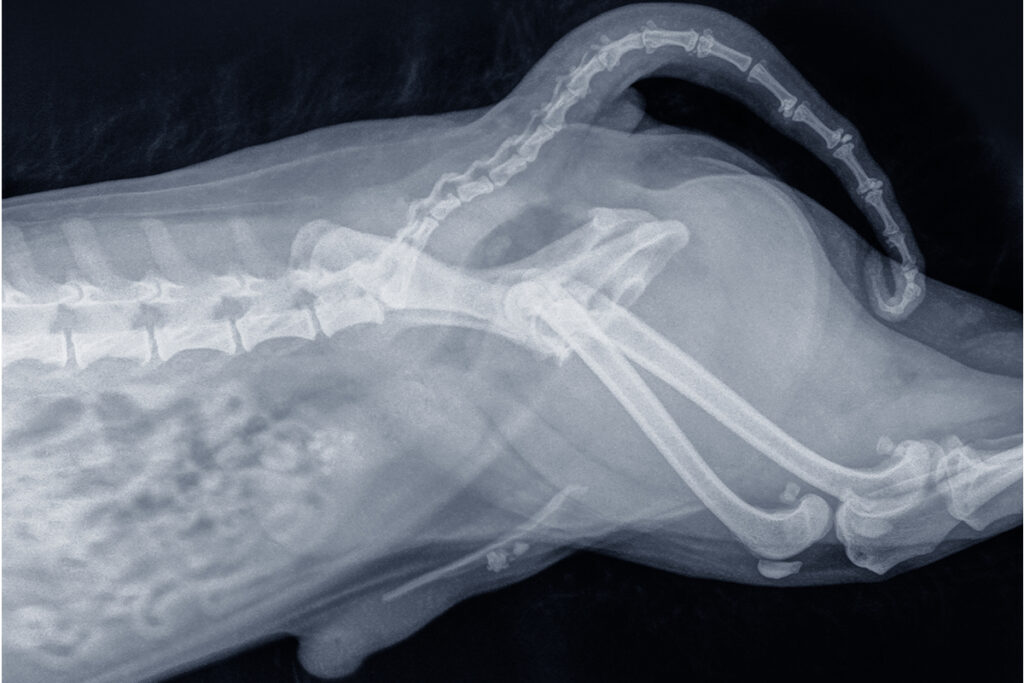

위·장 절개 수술

이물 섭취, 종양, 장폐색 등 응급 상황에서 필요한 수술입니다. 정밀한 수술과 철저한 통증 관리로 회복 부담을 줄입니다.